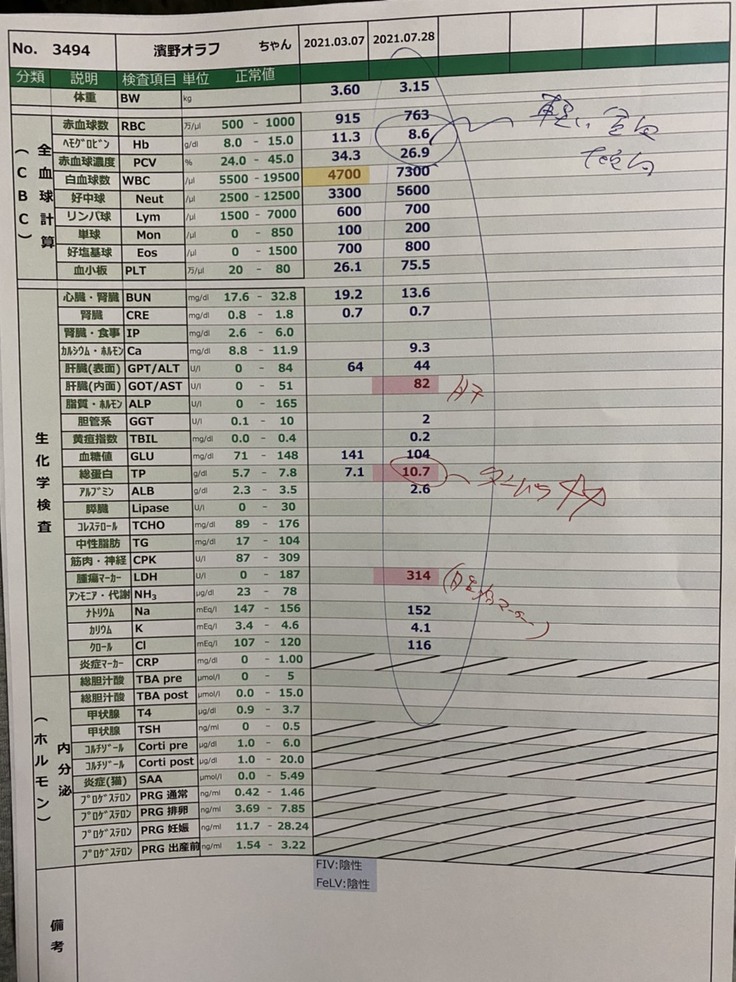

7月28日

血液検査、超音波検査、FIP検査、細胞診を行いました。

「お腹にしこりがあります。この年齢で腫瘍の可能性は低い。FIPの可能性があります。」

FIP検査結果が出るのは約1週間後です。

普段鼻がピンクなのですが、貧血気味で白っぽくなっていました。

8月2日

オラフのFIP陽性の検査結果が出ました。

炎症度合いの数値も2000以上と正常値ではありませんでした。

FIP陽性が確定し、オラフの動きは悪くはなかったんですが、食欲は戻らなかったので再度B病院に行きました。

熱が40度あり、体重が3.3kg→3.0kgまで減っていました。

血液検査の結果も前回より貧血値やA/G比が悪くなっていました。

「新薬に切り替えたほうがいいです。」と言われました。